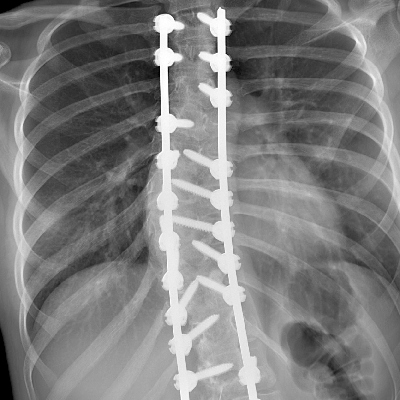

Sandra od urodzenia ma obniżone napięcie mięśniowe, asymetrię oraz zaburzenia SI. Mając ok. 5 lat zdiagnozowaliśmy u niej skoliozę, która z czasem bardzo postępowała. Pomimo ogromnego wysiłku i starań nie dało się jej zmniejszyć, dlatego musiała być operowana w wieku 12 lat. Sandra ma usztywniony prawie cały odcinek piersiowy i lędźwiowy. Niestety kilka miesięcy po bardzo skomplikowanej operacji pojawiły się codzienne bóle odcinków szyjnego i lędźwiowego, dlatego też wymaga ciągłego leczenia, rehabilitacji i terapii wielospecjalistycznej. Oprócz tego Sandra ma wadę wzroku, Zespół Aspergera, doszła również choroba genetyczna Zespół Ehlersa-Danlosa oraz leczy się na depresję. Dzięki Waszej pomocy Sandra może uczestniczyć między innymi w bardzo kosztownych turnusach rehabilitacyjnych, różnych terapiach, aby ratować zdrowie psychiczne oraz fizyczne. Każda nawet najmniejsza wpłata jest dla nas bardzo ważna i z całego serca Wam dziękujemy.